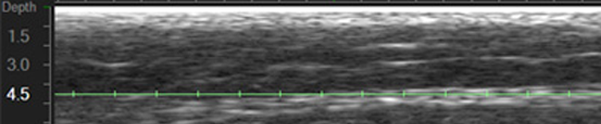

녹색선보다 한참 아래 흰색 근막이 보이시나요??

확대하면

거의 1.5-2mm 정도 차이가 날 정도로

근막이 깊게 위치하고 있는 것을 보실 수 있습니다.

울쎄라 팁중에 가장 깊은 4.5mm 팁을 사용해도 근막에 안 닿는 이유는

지방층이 너무 두껍기 때문입니다. (까만색이 지방!)